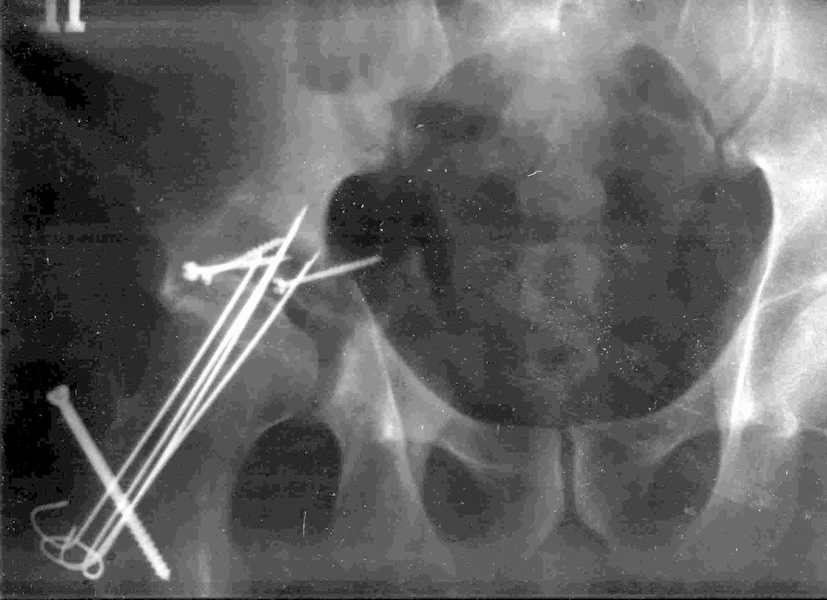

Мужчина 32 года, автотравма 6 недель назад. При поступлении был установлен диагноз "Ацетабулярный перелом". Вывих бедра не был установлен.

После установления вывиха бедра через 3 недели после травмы больному выполнена попытка открытой репозиции, остеосинтез вертлюжной впадины, Бедро фииксировано трансартикулярно спицами. После операции неврит седалищного нерва. В течение ещё 3-х недель после операции установлено что отломки не репонированы, вывих бедра не устранён (см. КТ и рентгенограмму), неврологической динамики нет. Возние вопрос о повторном оперативном вмешательстве по поводу чего разгорелись жаркие споры и сформировалось следующие мнения:1. Тотальное эндопротезирование с цементной фиксацией чашки протезом "ЭСИ" (другого протеза нет)2. Повторная открытая репозиция бедра с замещением дефектов вертлюжной впадины аутокостью с целью подготовки для последующего эндопротезирование. Предполагается фиксация тазобедренного сустава в послеоперационном периоде гипсовой повязкой или аппаратом внешней фиксации.Прошу высказать ваше мнение о тактике дальнейшего лечения пациента, о предложенных вариантах. Отдельный вопрос о возможности первичного тотального эндопротезирования при ацетабулярных переломах. (Лечащий врач настаивал перед первой операцией на выполнении тотального эндопротезирование с цементной фиксацией чашки через 3 недели после травмы)

Было бы существенным посмотреть обзорную R-грамму до операции. По данным послеоперационных снимков и КТ имеется низкий двухколонный перелом или

высокий Т-образный перелом с отрывом свода. Для уточнения необходиы косые проекции (Judet). Весь ли седалищный нерв молчит или только м/б порция?

Высылаю прямой обзорный и косой подвзошный снимки, косой запирательный неудовлетворительного качества.